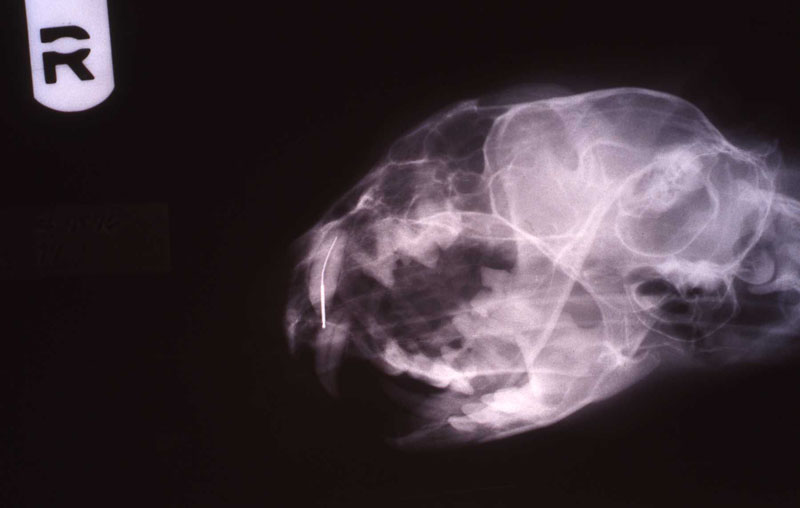

An 18 month old, 7.5 kg , female caracal (Caracal caracal caracal) new to the Milwaukee County zoo collection presented with a fractured right maxillary canine tooth during routine quarantine examination. The canine tooth had approximately 3 mm of its tip fractured off, the pulp chamber was exposed, and the tooth was darkened due to degeneration of of the pulpal tissue, and induction of food debris. There was no sign of an external drainage tract lesion. Radiographic examination revealed the presence of a periapical lesion 6mm by 7mm in diameter. The extra-oral surgical approach was chosen to debride the periapical lesion, resect the apex, and perform a retrograde fill in conjunction with the coronal or oblique endodontic fill.

lnteroperative and postoperative radiographs were obtained to verify endodontic working length and extent of endodontic fill.

The animal was reimmobilized using either a similar anesthetic regimen, or ketamine 6mg/kg and medetomidine (Domitor©, Pfizer Animal Health) 37 mcg/kg I.M., at 3 weeks, 14 months and 29 months. A small scar, approximately 1x4 mm, remains present at the incision site. Radiographs taken at each recheck showed healing of the periapical lesion, and normal bone repair in the surgical site.